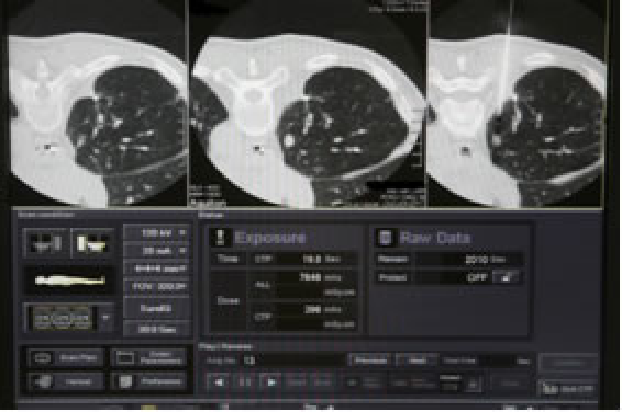

写真の解説:我々は最先端の技術が搭載されたIVR-CTを駆使し、モニター上に映し出されるCT画像を見ながら極めて正確に腫瘍にラジオ波治療用の針を穿刺することができます。

患者様にはまずCT台の上に仰向けもしくはうつぶせで寝ていただきます。IVR-CT装置を駆使し、CT画像を観察しながら電極針を病変に刺入します。その後、腫瘍を加熱して死滅させます。治療時間は、病変の数や大きさにより様々ではありますが、1~2時間程度で終わることが多いです。